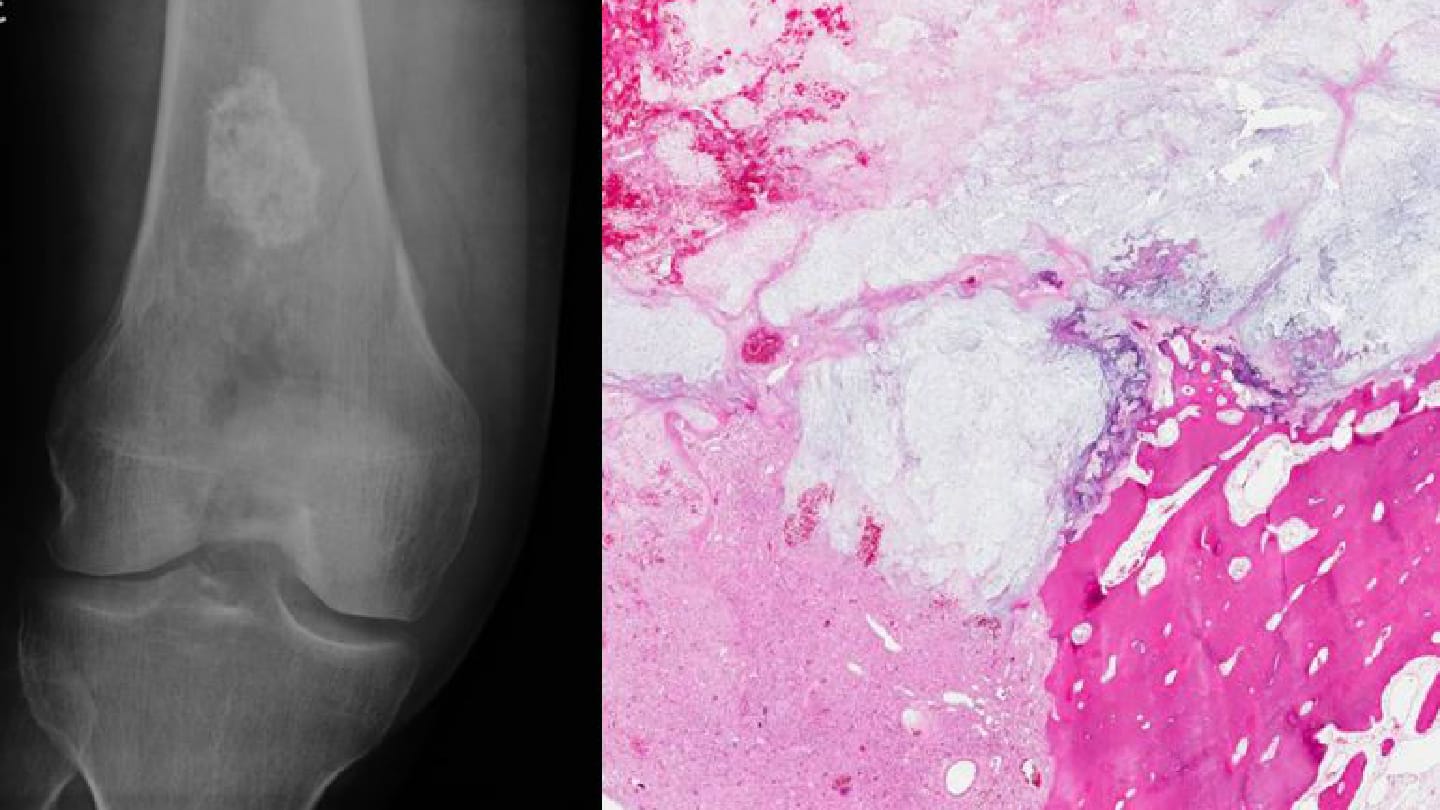

In my lectures, I often present two instructive cases of dedifferentiated chondrosarcoma, a biphasic tumor composed of a low-grade cartilaginous component and a high-grade sarcoma. In the first case, the biopsy contained only the cartilaginous portion. Without radiologic correlation, the diagnosis might have been limited to enchondroma or low-grade chondrosarcoma, completely missing the high-grade sarcoma – the more aggressive component with a higher risk of metastasis.

In the second case, I received only the high-grade sarcomatous element. It could easily have been misdiagnosed as an undifferentiated pleomorphic sarcoma of bone if I had not correlated with imaging that clearly demonstrated a well-delineated cartilaginous component consistent with dedifferentiated chondrosarcoma. These examples underscore how essential radiologic–pathologic correlation truly is.